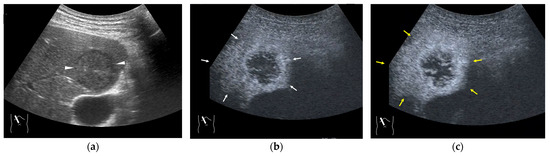

Currently, abdominal ultrasound is used in various ways, including contrast-enhanced elastography and endoscopic ultrasound, and is becoming a central part of the diagnosis of abdominal diseases. However, it is also true that there are still areas of abdominal diseases that have not been fully explored. It is necessary to focus on this area to advance the use of diagnostic ultrasound. For this reason, we are launching a Special Issue to collect related papers.

In this series, we will present cases with many lessons learned regarding liver, biliary, and pancreatic tumors, which are the main abdominal diseases, with a focus on external ultrasound and endoscopic ultrasound and will organize the information obtained to provide an objective and in-depth perspective on how to prevent misdiagnosis and draw conclusions that can be immediately applied to general clinical practice. To supplement this series, we will also include a detailed description of the peritoneum, mesentery, and omentum, which are always difficult to diagnose in daily clinical practice, as well as key points in the diagnosis of these pathologies.